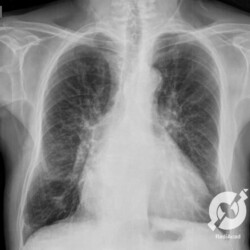

Aumento do volume cardíaco, inversão da circulação pulmonar, lesões intersticiais reticulares com linhas A de Kerley à esquerda e B de Kerley bilaterais e obliteração do seio costofrênico direito.